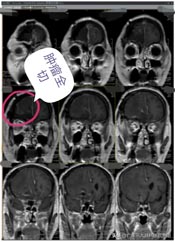

近段时间来,林阿姨头痛越来越重,偶尔还会出现小便失禁,林阿姨这才有所警觉。在医院头颅CT检查,显示:前颅底巨大占位,考虑脑膜瘤可能性大。林阿姨吓坏了,半辈子都平平安安,想不到脑子里居然有这么大的一个肿瘤。

孩子们也非常担忧,通过四处打听,林阿姨来到了广东三九脑科医院。进一步影像检查也提示是:前颅窝底巨大占位性病变,考虑脑膜瘤可能性大。

肿瘤体积巨大,占位明显,医院副院长、神经外五科主任鲁明和团队一起经过讨论,快速制定了安全且风险较小的手术方案,术中需要避开重要血管,尽最大可能全切除肿瘤。术前进行全脑血管造影,影像显示:前颅底异常染色,呈类圆形,肿瘤主要是由右侧脑膜中动脉前支、右侧眼动脉分支参与供血;决定先行肿瘤栓塞术,术后加压包扎送病人至手术室,行“前颅底巨大脑膜瘤切除术”。肿瘤周围血管丰富,已侵犯重要神经;导航准确定位,显微镜下见肿瘤起源于大脑镰及前颅底,阻断肿瘤血供后,先钨刀切除左侧额部部分肿瘤,再超吸切进行瘤内减压,最终镜下将肿瘤切除干净。